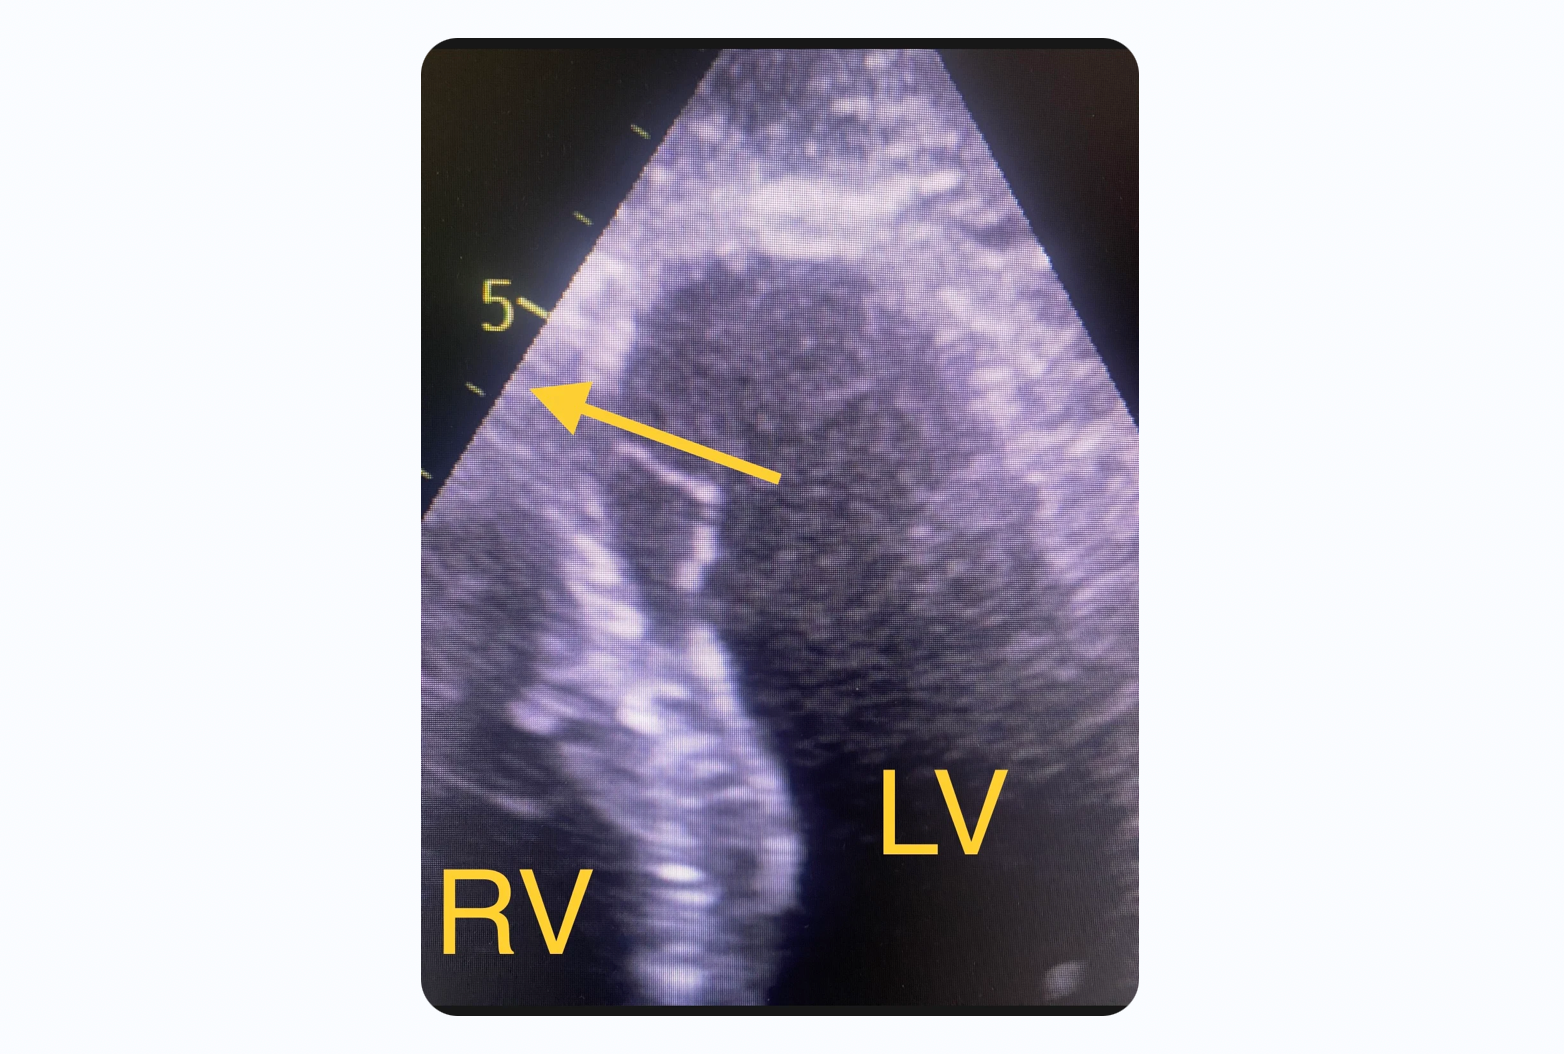

The above echo loop shows a high turbulence flow that traverses the distal interventricular septum. This is consistent with a ventricular septal rupture (VSR). Mechanical complications such as VSR and free wall rupture are associated with post infarct regional pericarditis. This patient as expected presented with a new harsh holosystolic murmur.

This image shows the direction of blood flow from the left ventricle (high pressure system) through the ventricular septal rupture to the right ventricle (low pressure system). If the defect is a large one, pressure across the defect will equalize quickly and the pressure gradient will be low. If the defect on the other hand is small, pressures will not equalize and a pressure gradient can be measured by doppler. The pressure gradient in this case was significant indicating that the defect is rather small. The larger the size of the defect the larger the shunt. Larger shunt volume means less blood exiting the left ventricle through the aortic valve and lower cardiac output.